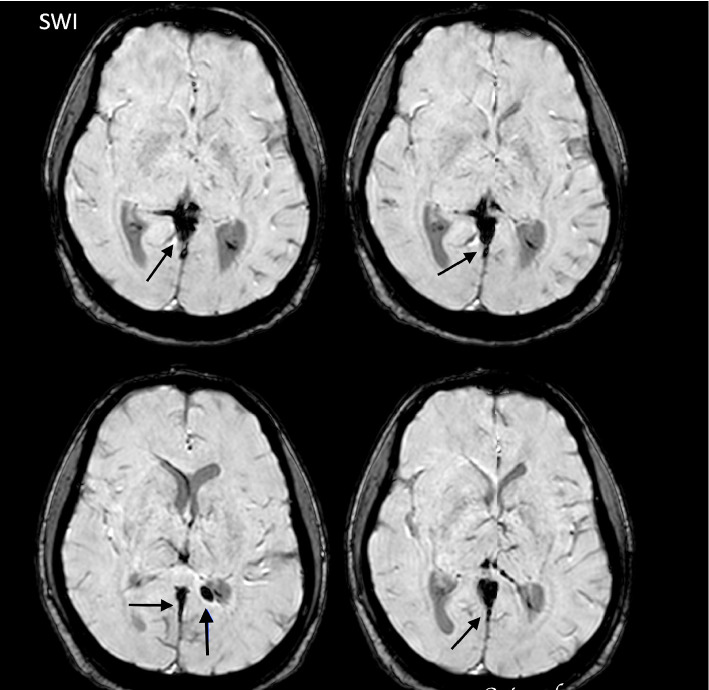

登革热由一种通过伊蚊传播的黄病毒引起,临床表现从轻微到严重不等。一些神经系统并发症,包括脑病和脑炎,已经被越来越多地认识到。在此,我们报告一例中心静脉血栓形成(CVT)作为登革热的感染后并发症。一名先前健康的38岁男性出现典型登革热症状,后来出现持续性头痛和视力障碍。神经学检查显示乳头水肿,影像学证实CVT累及上直窦。迅速开始抗凝治疗导致神经症状逐渐改善和血栓窦部分再通。我们的病例强调了在登革热感染中考虑血栓并发症的重要性,尽管出血表现占主导地位。了解登革热的病理生理学和适当的血栓事件管理对患者的良好预后至关重要。

Dengue fever, caused by a flavivirus transmitted through Aedes mosquitoes, presents a spectrum of clinical manifestations ranging from mild to severe. Several neurological complications, including encephalopathy and encephalitis, have been increasingly recognized. Here, we report a case of central venous thrombosis (CVT) as a postinfectious complication of dengue fever. A 38-year-old previously healthy male presented with classic dengue symptoms and later developed persistent headaches and visual disturbances. Neurological examination revealed papilledema, and imaging confirmed CVT involving the superior straight sinus. Prompt initiation of anticoagulant therapy led to gradual improvement in neurological symptoms and partial recanalization of the thrombosed sinus. Our case underscores the importance of considering thrombotic complications in dengue infections, despite the predominance of hemorrhagic manifestations. Understanding pathophysiology and appropriate management of thrombotic events in dengue fever is crucial for favorable patient outcomes.